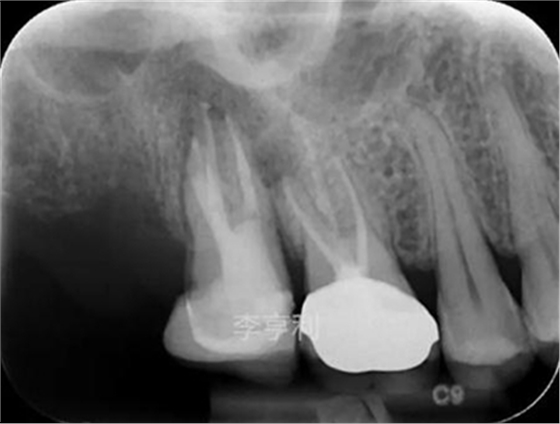

【輔助檢查】: CBCT見17冠部大面積充填物阻射影,接近髓室底,根管內充填物錐度尚可,距根尖均為2mm以內,根尖周大范圍阻射影主要在頰根區(qū)域,波及16的DB根尖區(qū)域,頰腭側骨板完整